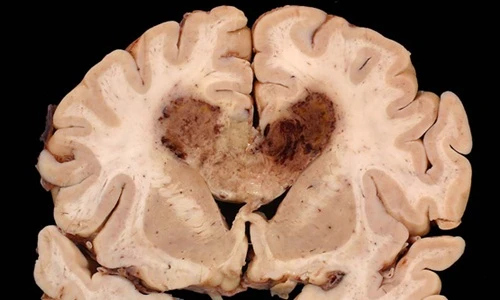

Ung thư Glioma: Đây là bệnh ung thư tế bào glio trong não. Bệnh không thường gặp nhưng cũng có tới 8% bệnh nhân bị do di truyền từ cha mẹ, ông bà... Ảnh: Ungbuouhungviet.

Ung thư Glioblastoma đây là thể nguy hiểm hơn của ung thư glioma trong đó tế bào không biệt hóa. Ảnh: ucsdnews.